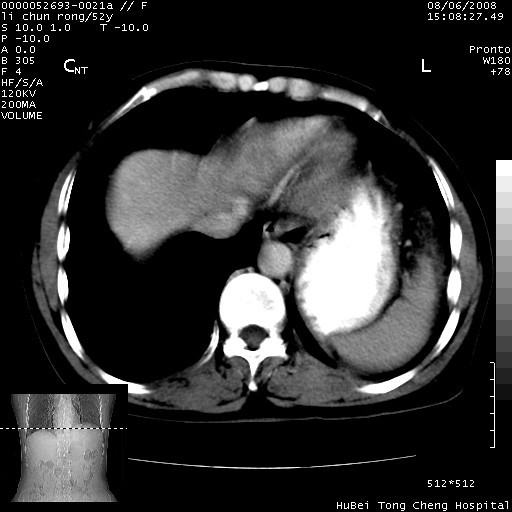

以下是引用云翔在2008-8-7 6:20:00的发言:[br]胰尾部囊性病变,考虑假囊肿,结合实验室检查疾病史

以下是引用zjzjr在2008-8-7 8:38:00的发言:[br]支持胰腺炎伴假囊肿形成,左肾小囊肿.少量腹水.

以下是引用随光逐影在2008-8-7 9:12:00的发言:[br]1)考虑胰腺炎伴假性囊肿形成可能性大;胰腺囊腺瘤待排。2)左肾小囊肿。3)少量腹水。